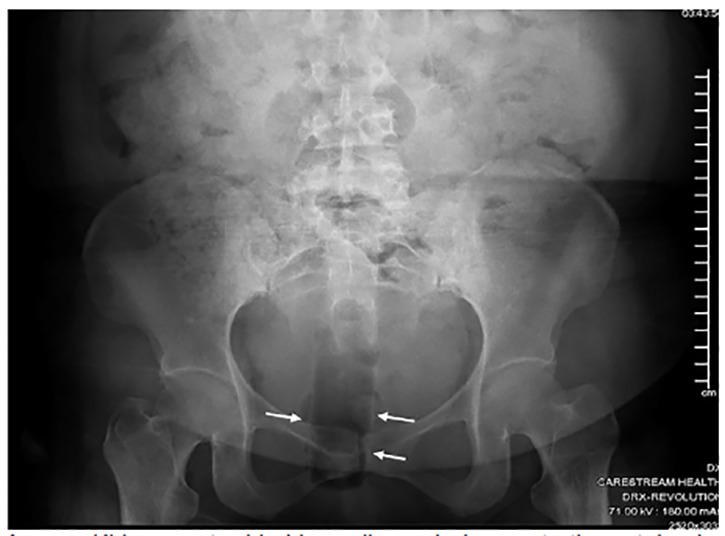

Rectal foreign bodies (RFB) pose a challenge to emergency physicians. Patients are not often forthcoming, which can lead to delays to intervention. Thus, RFBs require a heightened clinical suspicion. In the emergency department (ED), extraction may require creative methods to prevent need for surgical intervention.

The authors present a case of a successful extraction of a RFB in the ED and review of the literature.